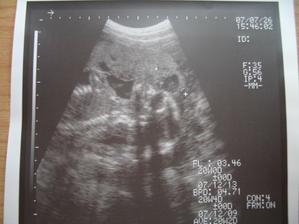

Dne 3.4.2007 to vypadá dle testů, že to vyšlo a my se snad dočkáme našeho vytouženého miminka a já nikdy nezapomenu děkovat a vážit si práce všeho personálu CAR u Apolináře. Dne 19.4.2007 nám bylo v CAR ultrazvukem potvrzeno, že opravdu čekáme naše vytoužené miminko. Dne 4.6.2007 jsme byli na genetickém UTZ ve 12+4.tt a UTZ dopadl na 1*. Dnes 26.7.2007 jsme byli na 3. ultrazvuku, jsme ve 20+2.tt a miminko je v naprostém pořádku. S maminkou už je to horši, ale snad všechno nakonec dobře dopadne. Dne 30.8.2007 jsme byli neplánovaně na 4. ultrazvuku a monitoru, protože maminka upadla na schodech, naštěstí je miminko v pořádku a neutrpělo žádnou újmu. Dnes 9.9.2007 jsme byli s tatínkem na 4D ultrazvuku v Gennetu Praha, máme krásné fotečky a DVD. Dozvěděli jsme se, že miminko v mém bříšku je holčička. Večer 9.9.2007 jsme naší holčičce vybrali jméno, je to Verunka.